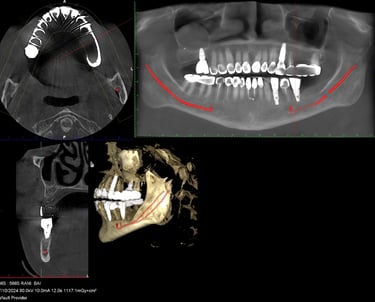

Dr. Z.R. Khan is an accomplished Oral Surgeon, proficient in a wide range of procedures from routine extractions and restorative and periodontal procedures to complex pre-prosthetic surgeries like ridge augmentation and sinus lifts for implant placement.